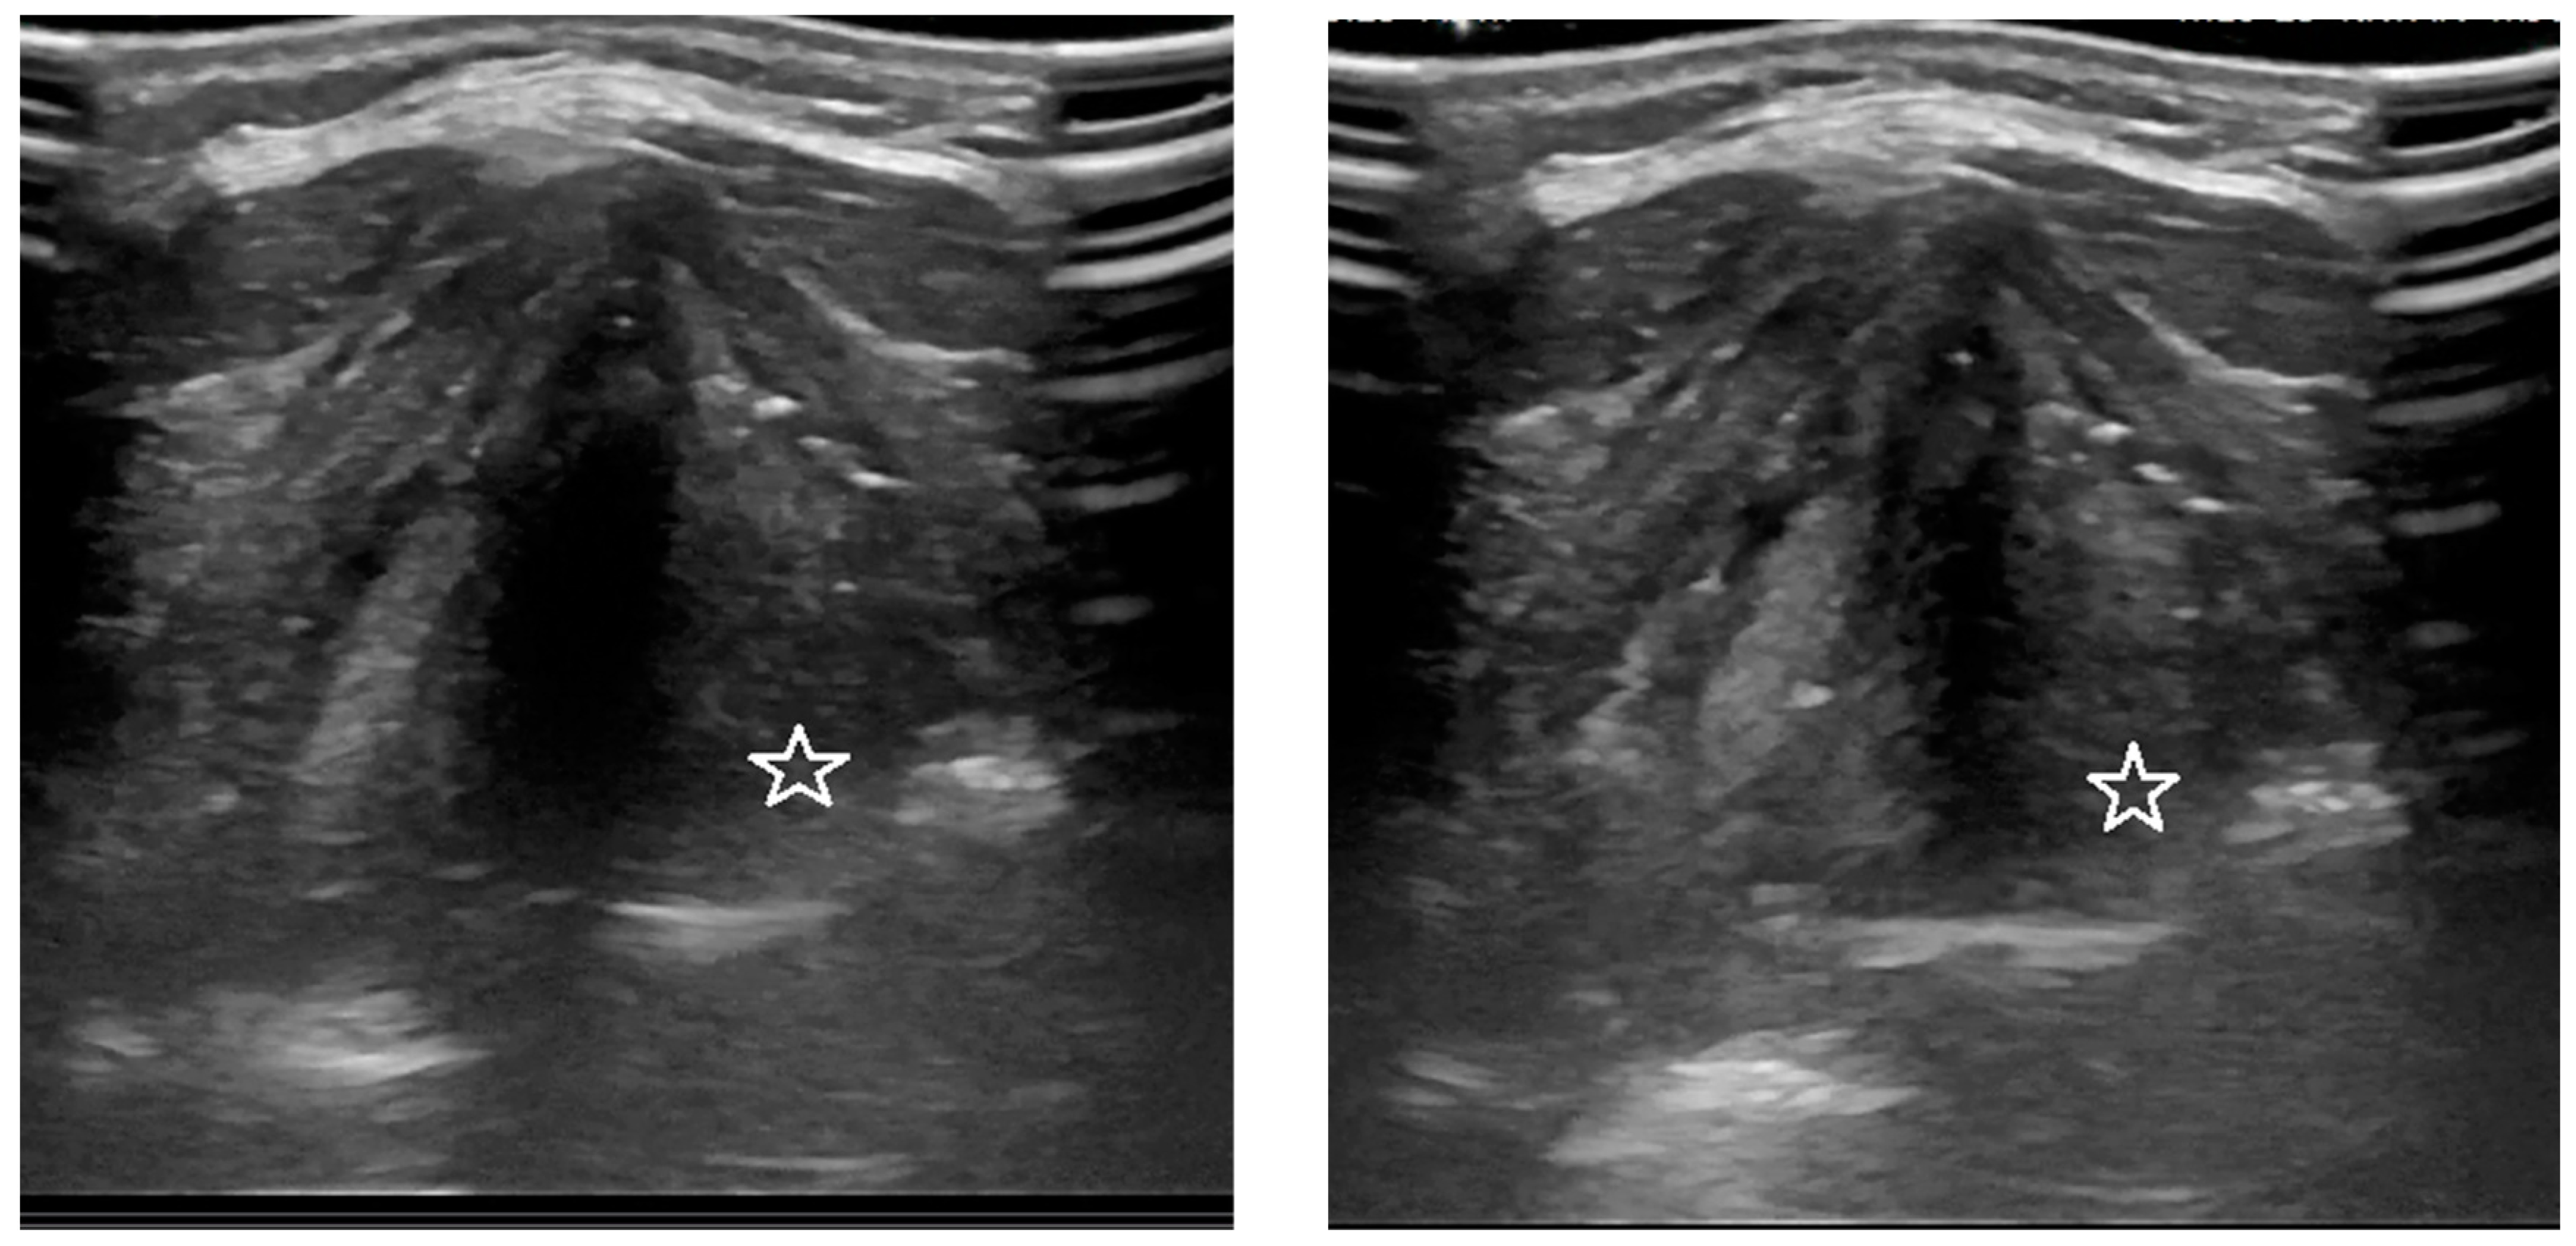

3.1. Analysis of the Qualitative Data Obtained during Ultrasound and MRI in Patients with Goiter Compared to Direct Laryngoscopy